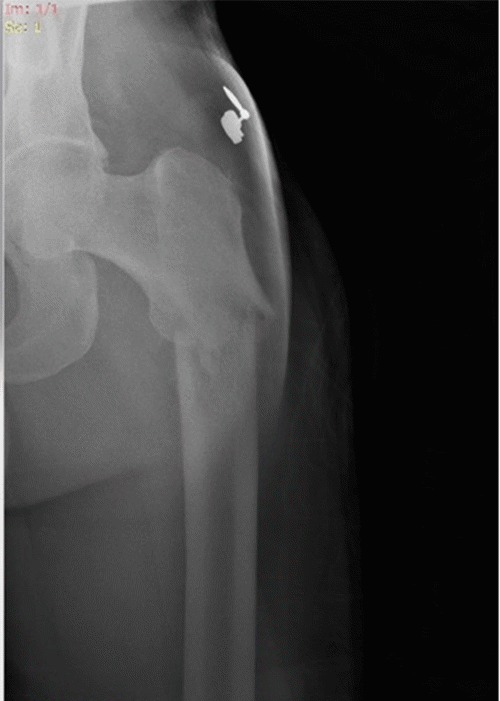

The patient was eventually discharged on POD 7. The final pathological staging of his sigmoid primary was Stage IV adenocarcinoma, pT3 N2b M1, with wild-type BRAF, KRAS, and NRAS. The bone biopsy revealed poorly differentiated adenocarcinoma consistent with a colorectal origin (Figure 3). Subsequent positron emission tomography-computed tomography (PET-CT) demonstrated extensive metastatic disease, including diffuse hypermetabolic activity in the peritoneal lining of the pelvis and widespread skeletal involvement. The surgically repaired pathological fracture of the left femur was noted, with associated lytic lesions (Figure 4). Numerous additional hypermetabolic foci were identified throughout the axial and appendicular skeleton, consistent with disseminated metastatic spread from the primary colorectal malignancy. The patient received induction chemotherapy with FOLFOX 6 plus bevacizumab (AVASTIN) and palliative radiation therapy. Despite aggressive multimodal treatment, his disease progressed, and he ultimately succumbed to complications of metastatic cancer seven months after his initial surgical resection.

Figure 4. Postoperative PET-CT Demonstrating Hypermetabolic Activity at Left Femoral Fracture Site. Published with Permission

Fused PET-CT images of the left femur obtained following orthopedic fixation. The image demonstrates intense focal fluorodeoxyglucose (FDG) uptake (SUVmax 19.30, arrow) at the site of the pathological fracture and surgical repair, consistent with metabolically active metastatic adenocarcinoma. Note the associated expansile osteolytic destruction and adjacent soft tissue involvement